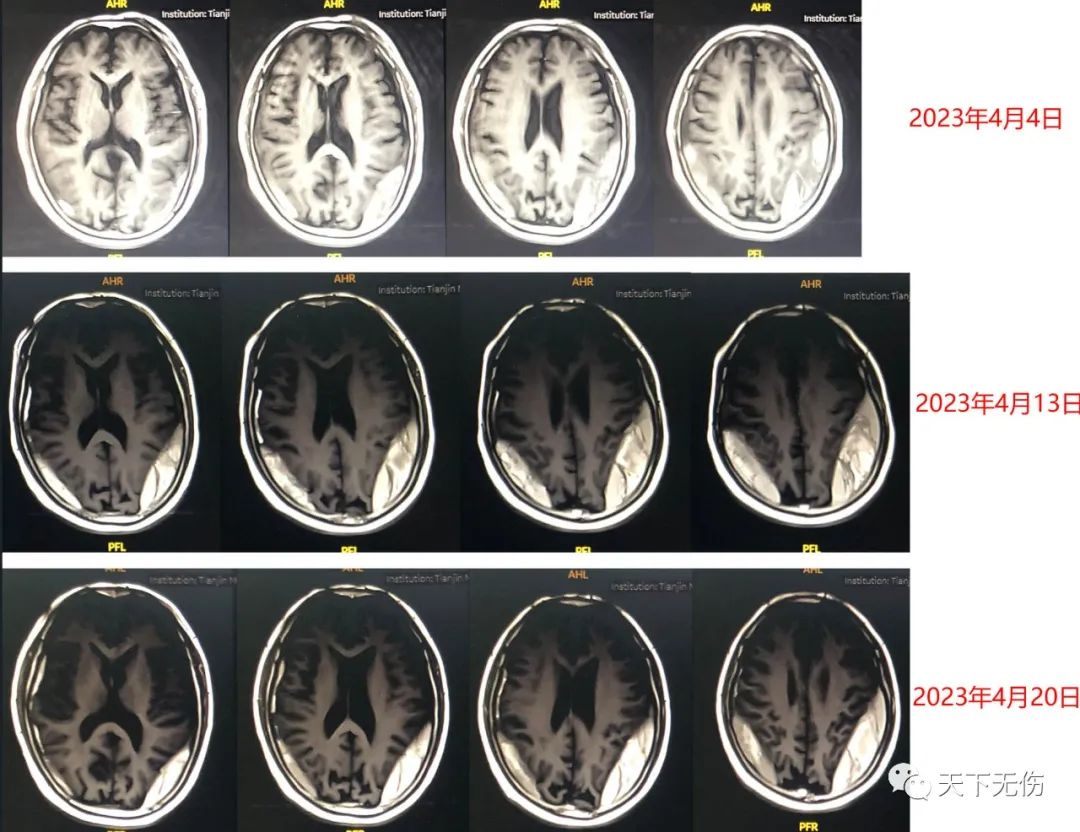

我了解他的治疗史后,尽快收治他住院治疗并于4月4日开始给他阿托伐他汀钙联合小剂量糖皮质激素治疗。大爷来的时候还是平车推着来的,治疗了仅3天,就可以下地行走了。大家都非常乐观,但治疗7天后的血肿复查结果却显示血肿似乎没有减少,还有所增大。我和家属都感到失望。我综合自己多例难治性慢性硬膜下血肿患者的治疗经验,劝家属再延长住院一周,然后在他汀加激素的基础上调整了方案,结果老人家每天的状态都在进步,行走也基本正常了。昨日是治疗的第14天,我和他的主管医生都在焦急地等待他的复查结果,结果确证,他的血肿在稳定缩小(图),我安排他今天出院回家,一家人千恩万谢地走了。